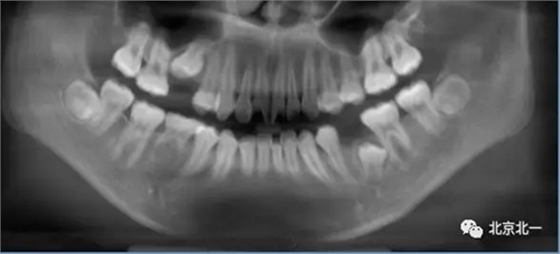

術(shù)后拍片